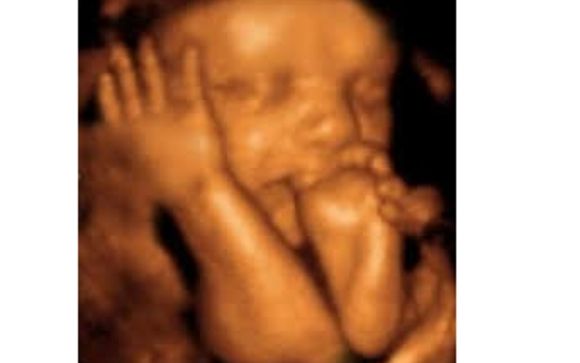

Precious Moments 3d 4d Ultrasound

Prenatal Ultrasounds Hdlive 3d Ultrasound And 4d Ultrasound 12